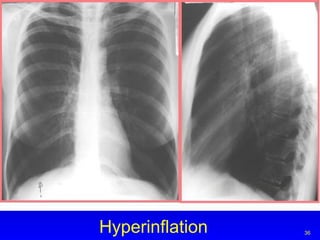

Hyperinflation